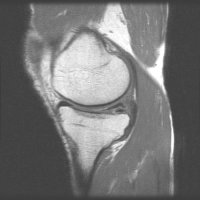

반월상연골파열이 의심된다면 치료를 서두르는 것이 중요하겠죠. 반월상연골파열을 검사하기 위해 신천동관절병원 21세기병원에서는 이학적검사, 영상의학적 검사 등을 시행하지만 보통 반월상연골파열은 MRI

할 수 있으며, 진단적 관절경으로 쉽게 확인 할 수 있습니다. MRI 또는 진단적 관절경에서 반월상 연골의 파열이 발견되면, 관절경으로 수술을 시행하게 됩니다 파열된 연골편을 절제 (부분 절제술